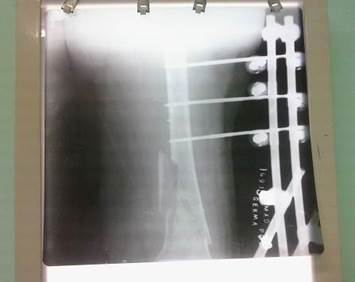

El tiempo quirúrgico fue de 45 minutos y se administró antimicrobianos profilácticos del tipo de la cefazolina a dosis de un gramo endovenoso en dosis única. Al terminar la intervención quirúrgica se realizó proyección radiográfica en vista anteroposterior donde se observó alineación de la fractura (Figura 4).